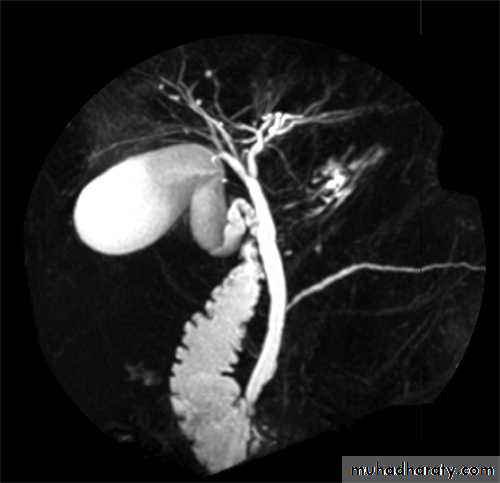

MRCP

• non-invasive

• no contrast.Gall stone & cholecystitis

Obstructive jaundice

ERCP & MRCP